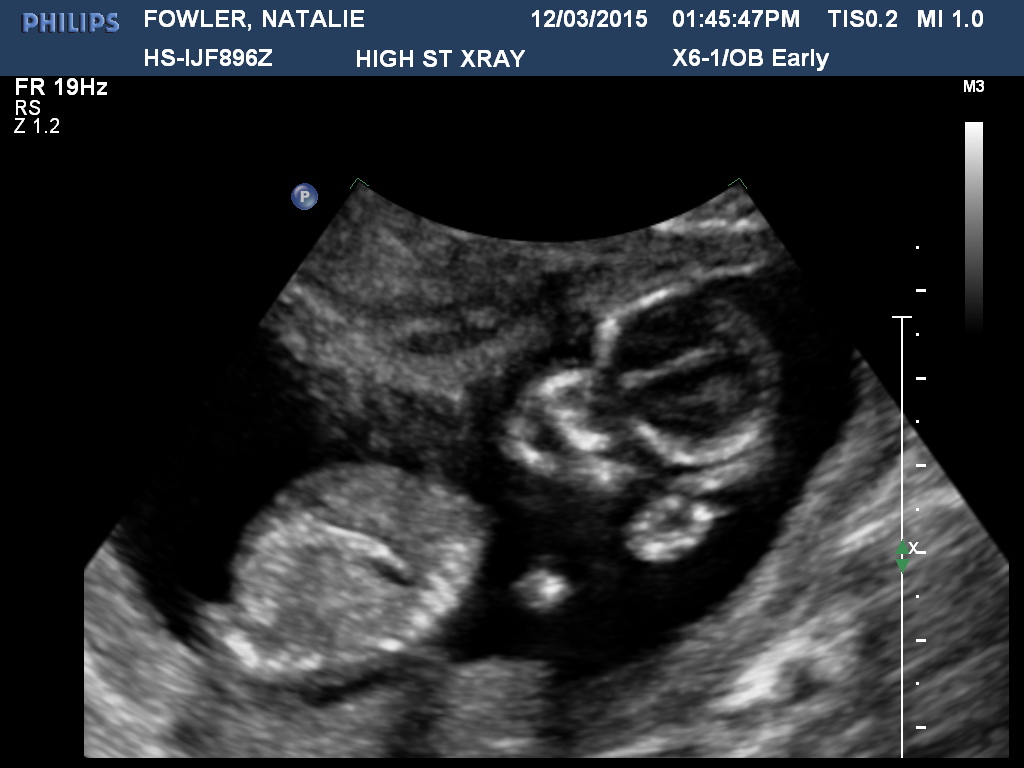

Thank you so much :) I'm not sure if this is the baby's nub but I thought I will post anyway :) Attachment 24232

I think the nub is a bit higher. Careful boy lean. Lots going on doen there

Had another scan done today and two techs said 80% girl :babyf: